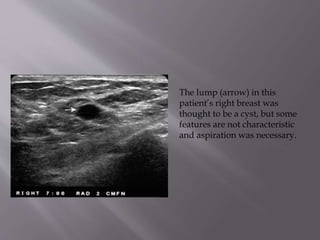

The lump (arrow) in this

patient’s right breast was

thought to be a cyst, but some

features are not characteristic

and aspiration was necessary.